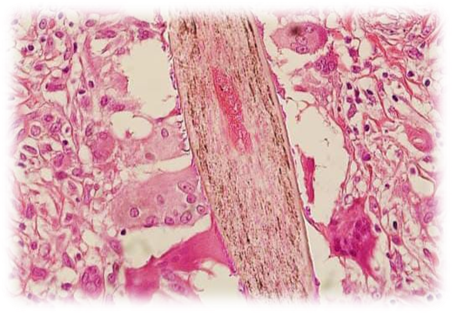

3. Histopathological Examination

In rare or severe cases, a biopsy of the affected follicle may be performed for histopathology. This helps distinguish folliculitis from other follicular disorders, such as:

• Acne vulgaris

• Psoriasis

• Lichen planopilaris

• Cutaneous fungal infections

Microscopic examination may reveal neutrophilic infiltration, abscess formation within the follicle, and perivascular inflammation, which confirms folliculitis.